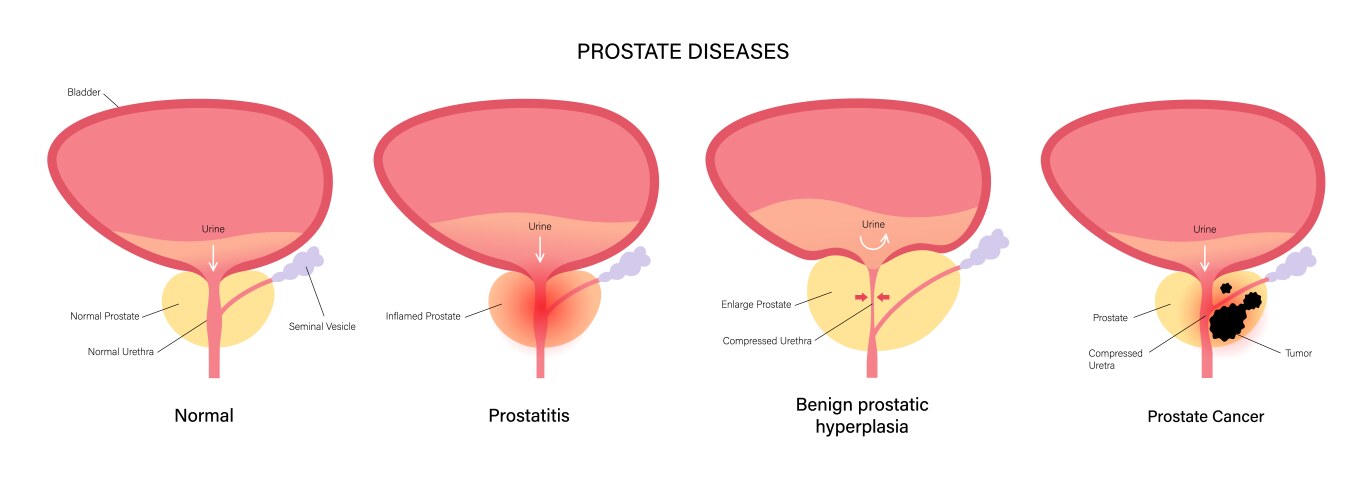

- Bph

- Prostate

- Anatomy

- Bladder

- Cancer

- Disease

- Prostatitis

- Tumor

- Gland

- Organ

- Types

- Urology

- Urethra